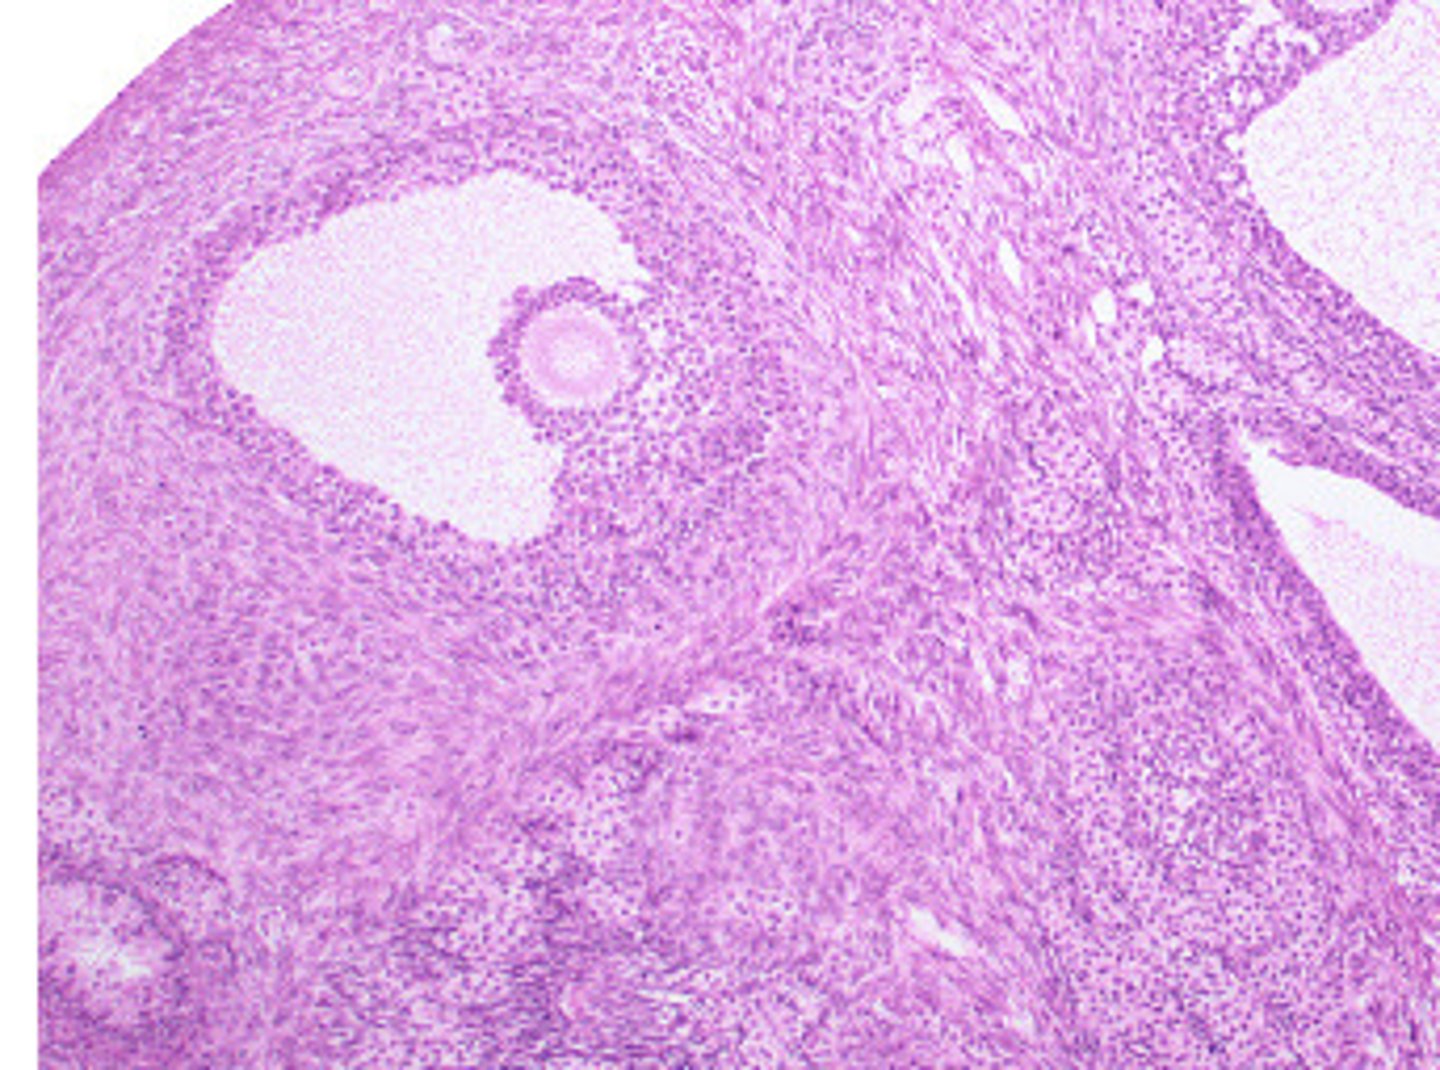

Ovary: Progesterone/Estrogen, Inhibin, Relaxin

Name this organ and hormones produced here

Mature Follicle

Blue arrow (general structure)

Oocyte

orange arrow

Follicle Cells

green arrow